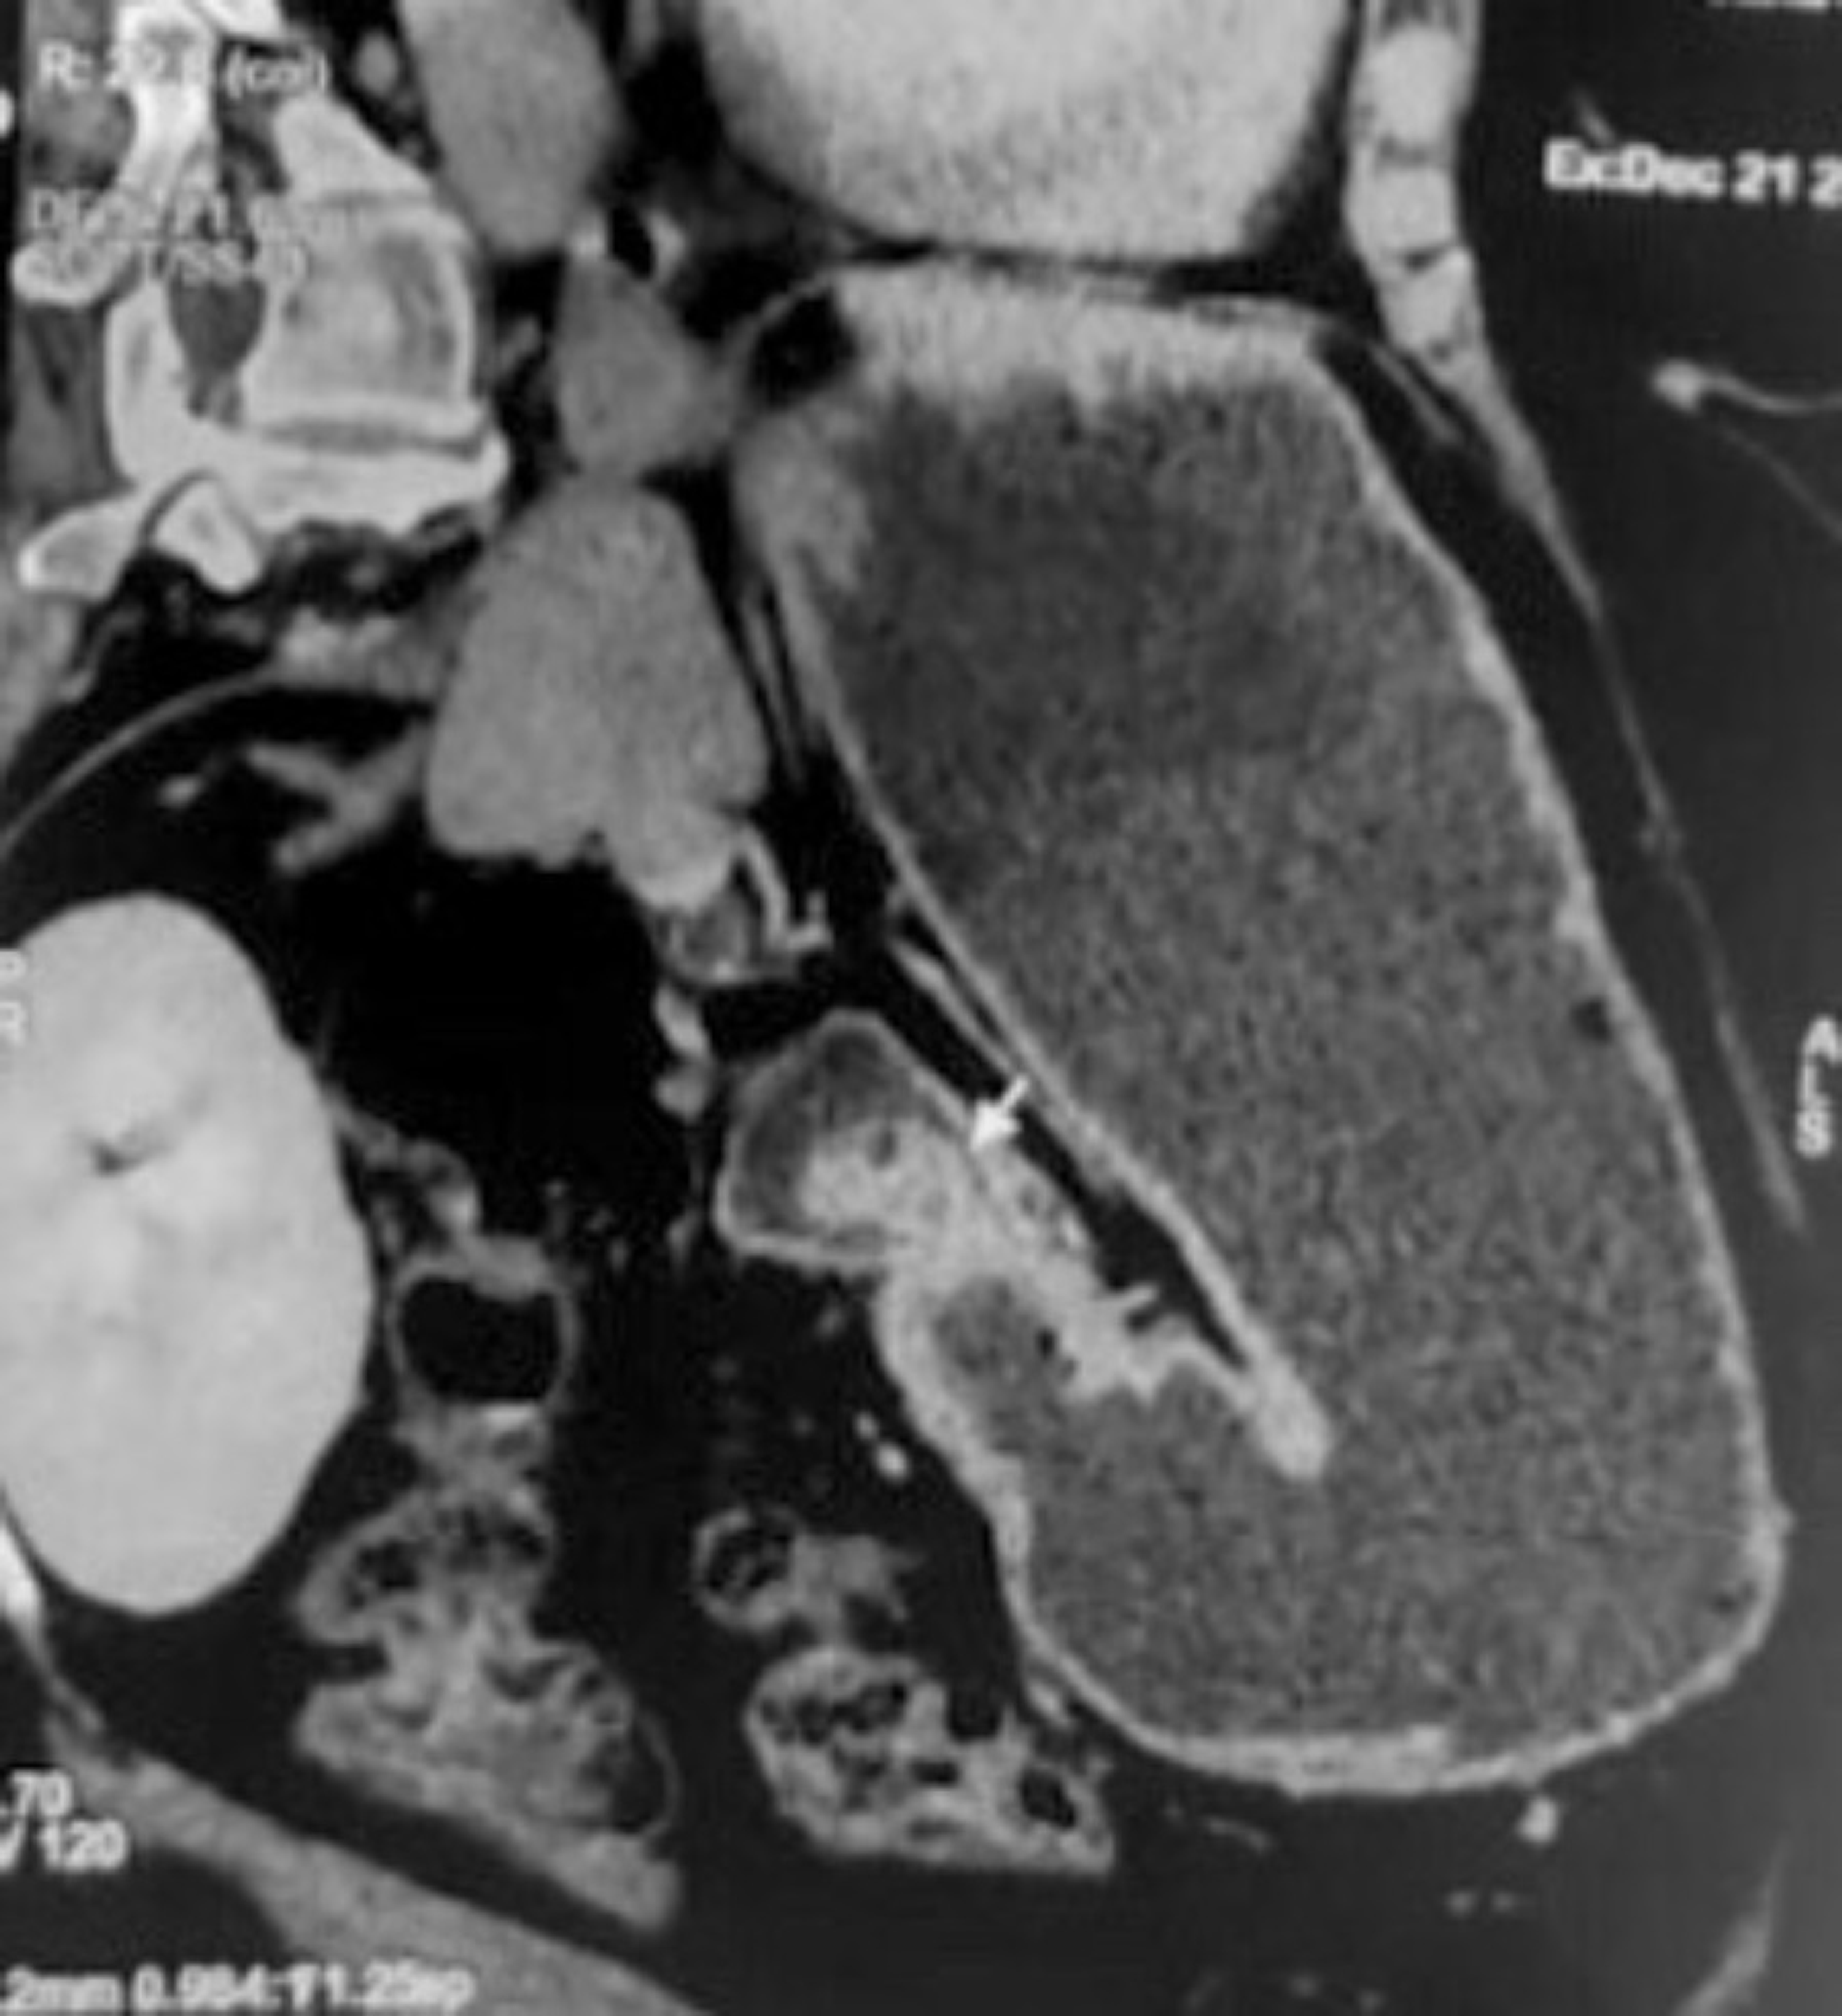

Brunner's Gland Hyperplasia and Hamartoma Imaging Features with

Brunner's Gland Hyperplasia and Hamartoma Imaging Features with Brunner Gland Hamartoma Stomach Web upper endoscopy was notable for a 12 mm pedunculated polyp in the duodenal bulb intermittently secreting opaque white fluid;. Web brunner’s gland hamartoma (bgh) is a rare benign tumour formed from a proliferation of brunner’s glands, typically forming a. Web brunner's gland hamartoma is a benign tumor of the duodenum, but has malignant potential with a very low risk. Brunner Gland Hamartoma Stomach.

Brunner's Gland Hyperplasia and Hamartoma Imaging Features with Brunner Gland Hamartoma Stomach Web brunner's gland hamartoma is a benign tumor of the duodenum, but has malignant potential with a very low risk of progression into. Web brunner’s gland hamartoma (bgh) is a rare benign tumour formed from a proliferation of brunner’s glands, typically forming a. Web upper endoscopy was notable for a 12 mm pedunculated polyp in the duodenal bulb intermittently secreting. Brunner Gland Hamartoma Stomach.

Brunner's Gland Hyperplasia and Hamartoma Imaging Features with Brunner Gland Hamartoma Stomach Web brunner’s gland hamartoma (bgh) is a rare benign tumour formed from a proliferation of brunner’s glands, typically forming a. Web upper endoscopy was notable for a 12 mm pedunculated polyp in the duodenal bulb intermittently secreting opaque white fluid;. Web brunner's gland hamartoma is a benign tumor of the duodenum, but has malignant potential with a very low risk. Brunner Gland Hamartoma Stomach.

Brunner's Gland Hyperplasia and Hamartoma Imaging Features with Brunner Gland Hamartoma Stomach Web brunner's gland hamartoma is a benign tumor of the duodenum, but has malignant potential with a very low risk of progression into. Web upper endoscopy was notable for a 12 mm pedunculated polyp in the duodenal bulb intermittently secreting opaque white fluid;. Web brunner’s gland hamartoma (bgh) is a rare benign tumour formed from a proliferation of brunner’s glands,. Brunner Gland Hamartoma Stomach.